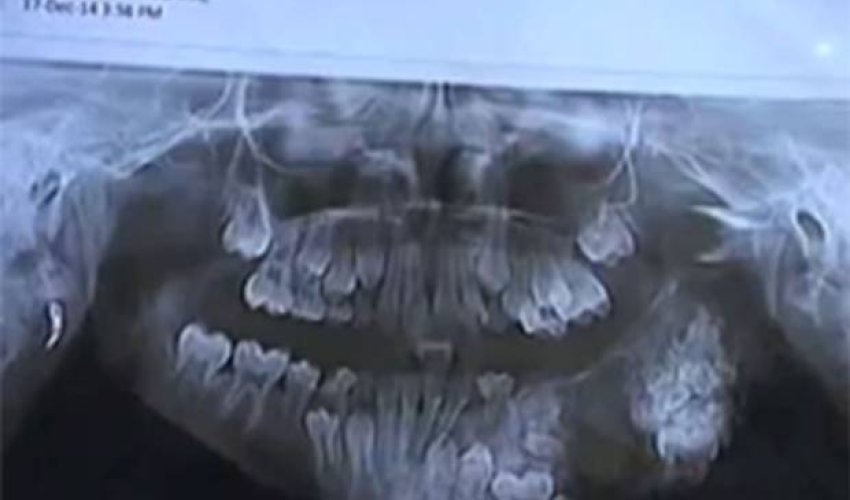

On Friday, a seven-year-old child had 80 teeth removed from his upper jaw after nearly four hours of surgery at the Maharaja Yeshwantrao (MY) Hospital in the city of Indore, Madhya Pradesh.

Dr Maheshwari told The Times of India, "The patient had visited us five days ago with abscess in upper jaw. Upon medical investigations, it was diagnosed a case of odontoma. We planned the surgery and removed 80 teeth after clearing abscess, which is rare in tender age."

Odontoma is a rare type of tumor affecting the jaw or gums that sees a concentration of tooth-like structures.

Local reports named the boy as Vivek. He had apparently developed a tumour on the left side of his mouth and was taken to MY hospital after treatment in his village failed to remedy his situation.